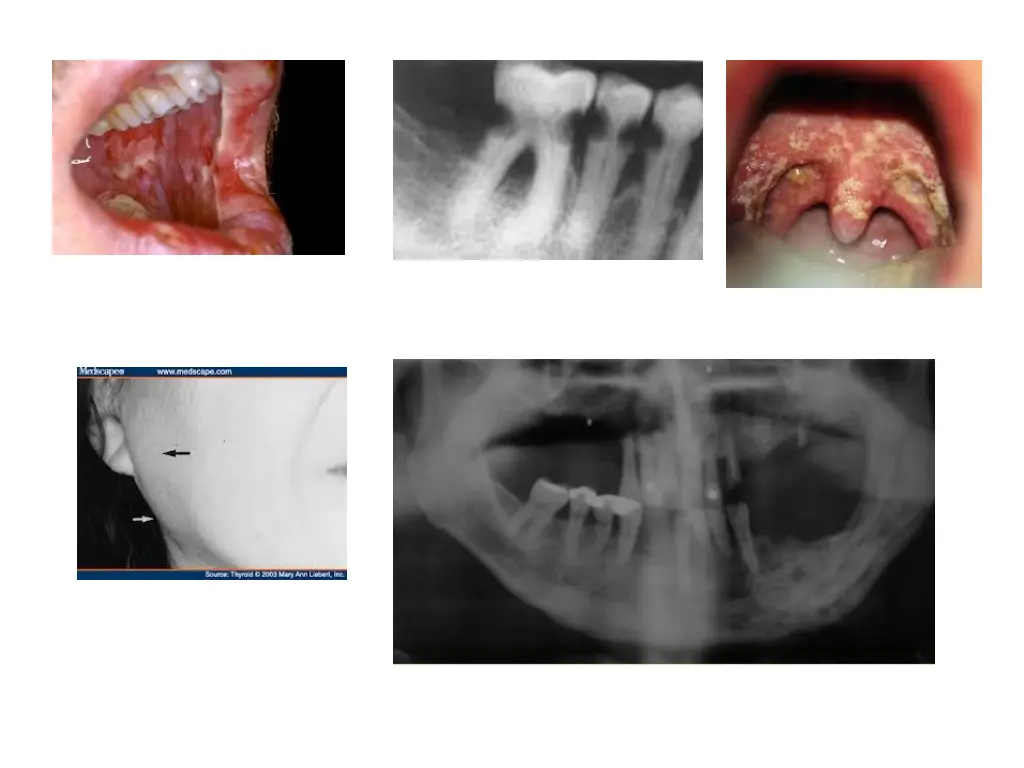

Mucoceles Is a clinical term that describes swelling caused by accumulation of saliva at site of traumatized or obstructed minor salivary gland duct Classified as extravasation and retention types A large form of mucocele located in floor of mouth is known as ranula

Mucocele Extravasation mucocele: results from trauma to minor glands. Laceration leads to pooling of saliva in adjacent submucosal tissue and consequent swelling Retention mucocele: due to obstruction of minor salivary gland duct by calculus or due to contraction of scar tissue around injured minor salivary gland duct Blockage causes accumulation of saliva and dilation of duct Eventually, an aneurysm like lesion forms, which can be lined by ept of dilated duct

Clinical presentation Extravasation type most frequently occur on lower lip, other regions being buccal mucosa, tongue, FOM,retromolar region Retention cyst: palate or FOM h/o trauma followed by development of lesion Present as discrete painless smooth surfaced swellings ranging from few mm to cm Superficial lesions always have a bluish hue Lesions size vary over time Pts frequently traumatize superficial one, allowing to drain and deflate In these circumstances, they recur

Treatment Surgical excision Removal of associated salivary glands is essential to prevent recurrence Surgical removal may traumatize adjacent glands Intralesional injections of corticosteroids have been successfully used

Ranula Is a large mucocele located on the FOM May be extravasation or retention type Are most commonly associated with sublingual salivary gland duct Etiology: trauma Obstructed salivary gland or ductal aneurysm

Clinical presentation Presents as painless, slow growing, soft and movable mass located in the FOM Lesion forms on one side of lingual frenum If lesion extends deep into soft tissue, it can cross the midline Superficial ranulas can have a blue hue Deep seated one have normal appearing mucosa Large lesion cause deviation of tongue Deep lesion that herniates through the mylohyoid muscle and extends along the facial planes is referred to as plunging ranula and may become large, extending into the neck

Treatment Treated surgically Marsupialization unroofs the lesion, for smaller lesions Recurrent cases, excision of lesion and gland is recommended Intralesional injections of corticosteroids have been successfully used in treatment

Necrotizing sialometaplasia Is a benign self-limiting reactive inflammatory disorder of salivary tissue this lesion mimics a malignancy Initiated by a local ischemic event C/f: has a rapid onset Occur predominantly on palate Lesions initially start as a tender erythematous nodule Once mucosa breaks down, a deep ulceration with yellowish base fprms Even though lesions can be large and deep, pts experience moderate degree of pain

Lesions often occur shortly after oral surgical procedures, restorative dentistry or administration of LA Lesions may also develop weeks after a dental procedure or trauma Treatment: self limiting, lasts approx 6 weeks and heals by secondary intention No specific treatment required Debridement and saline rinses may help healing